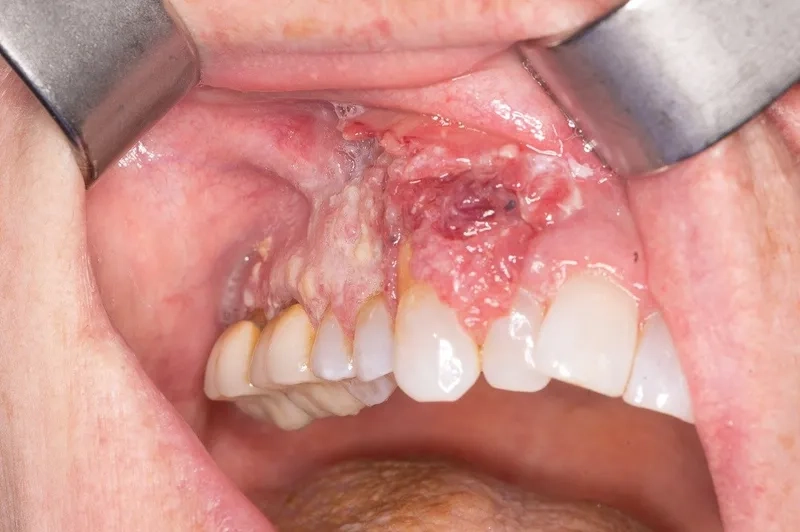

Clinical oral cancer pictures for awareness

• One of the most common mouth cancer symptoms is a sore, ulcer, or irritation in the mouth or on the lip that does not heal.

• Be aware of red or white patches (erythroplakia or leukoplakia) on the lining of your mouth, gums, or as part of tongue cancer symptoms.